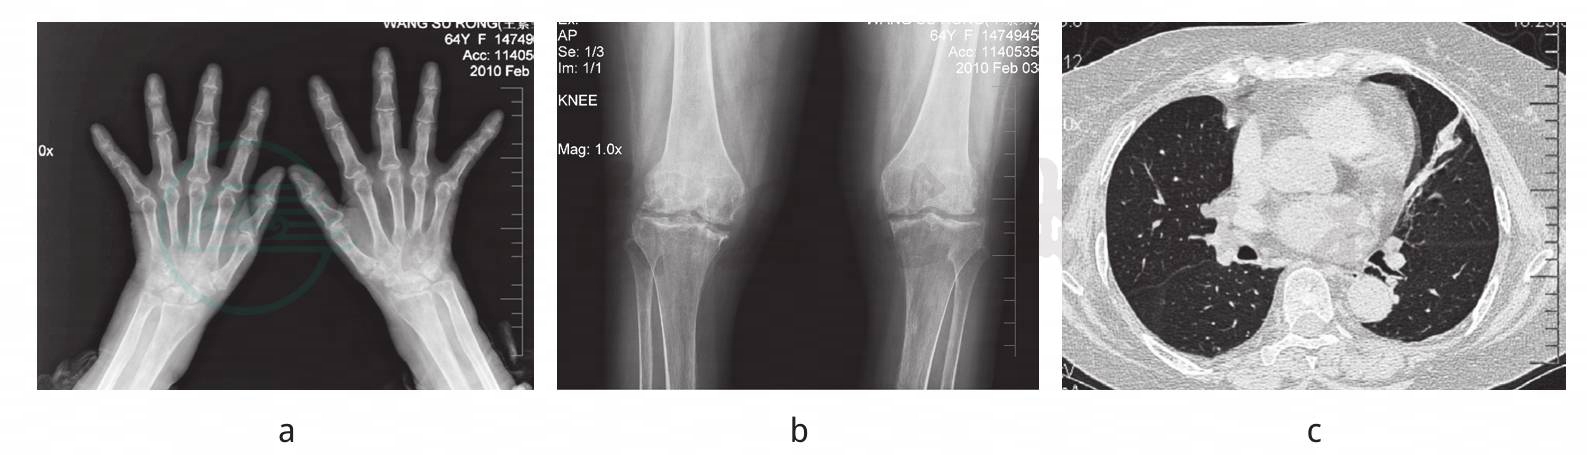

双手相(图1a):明显骨质疏松,双手第2、3MCP关节间隙狭窄及破坏。双膝相(图1b):明显骨质疏松及破坏,呈虫蚀样。肺CT(图1c):左肺条带状影。

a.双手多个掌指关节、近端指间关节及腕关节骨破坏及明显骨质疏松;b.双膝关节面骨破坏明显,胫骨平台塌陷,伴软骨下骨硬化及骨质疏松;c.肺CT:左肺条带状影